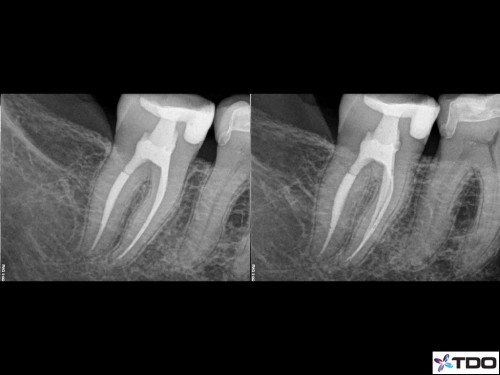

Yesterdays complete. Findings were a DMR crack with no associated isolated probings and recurrent caries under the old M resin. Stone removal. 3 mesial canals and resin core. Advised a crown.